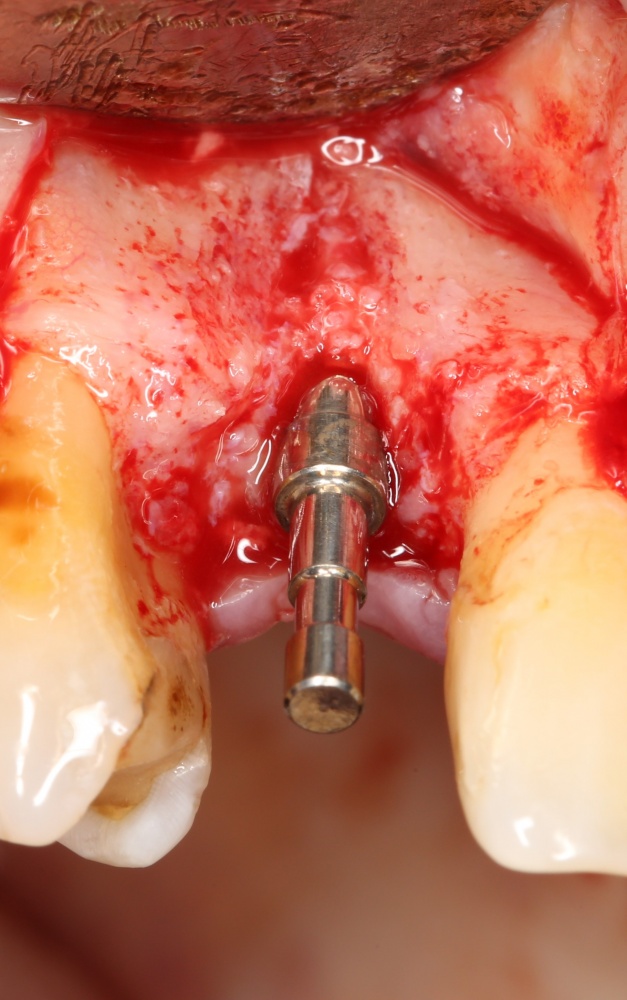

Рекомендации по установке имплантов. Для всех. Часть V.